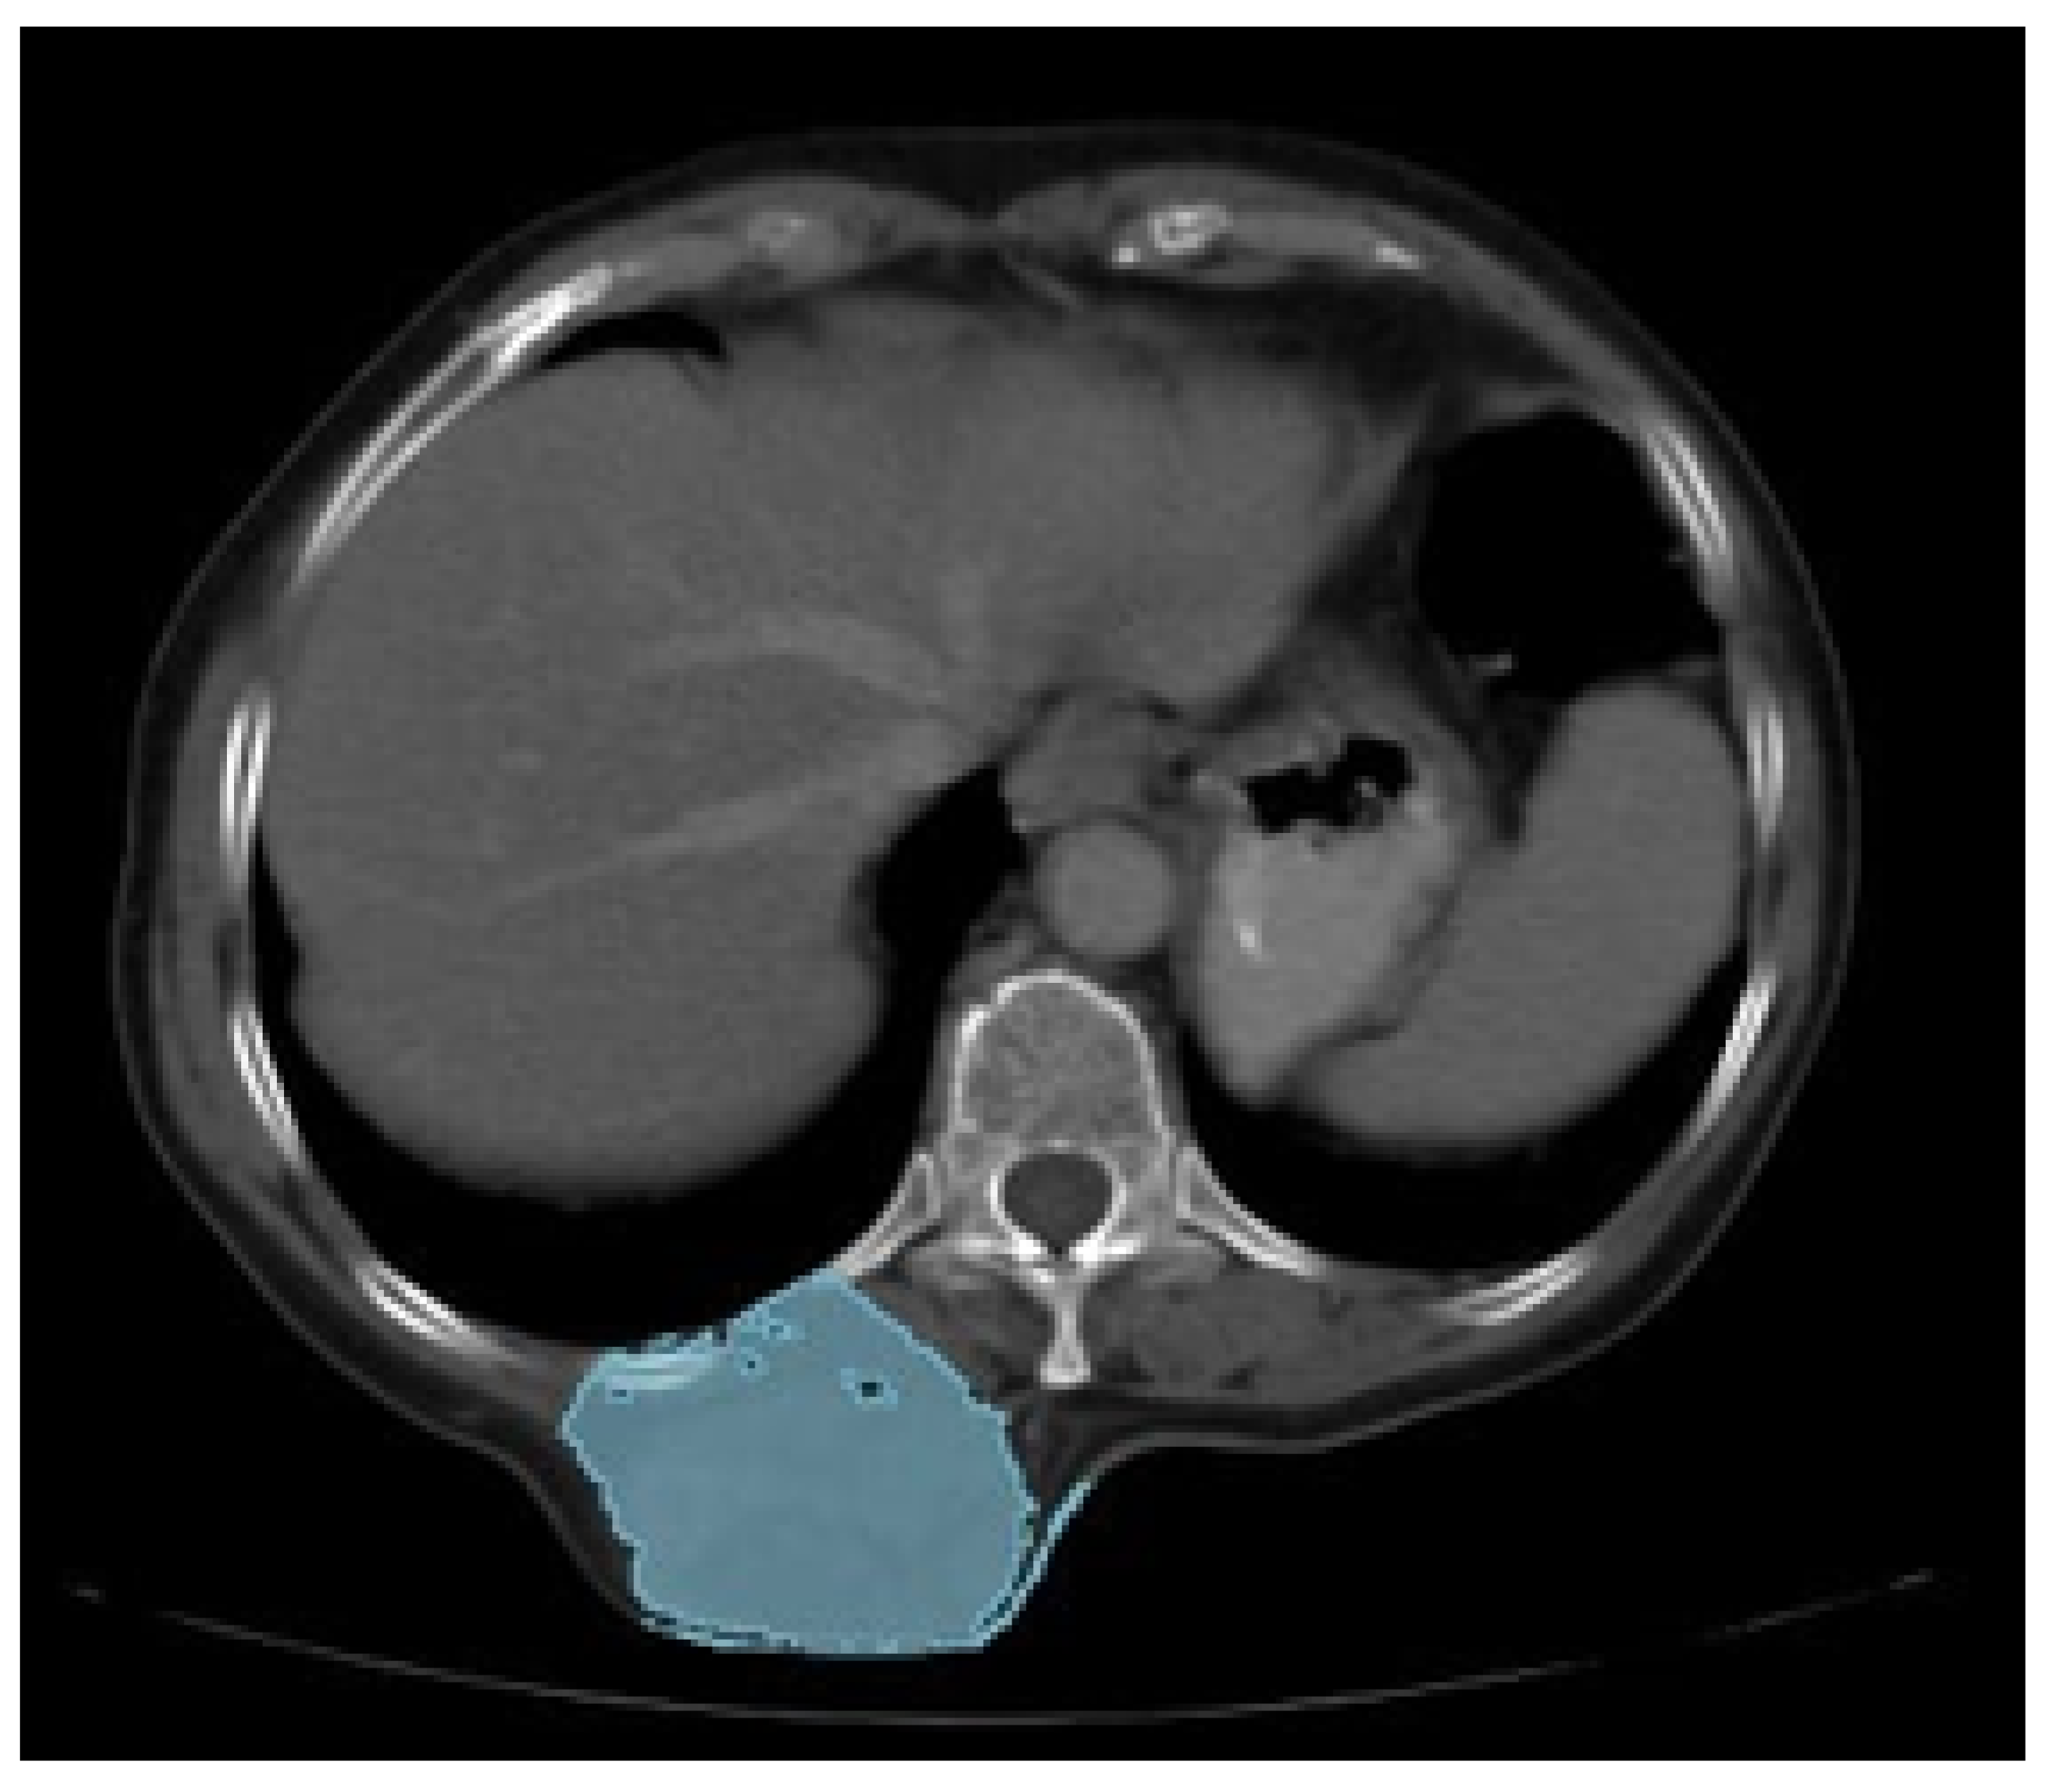

3.5. Case 5: Posterior Chest Tumour

3.5.1. Diagnosis and Analysis